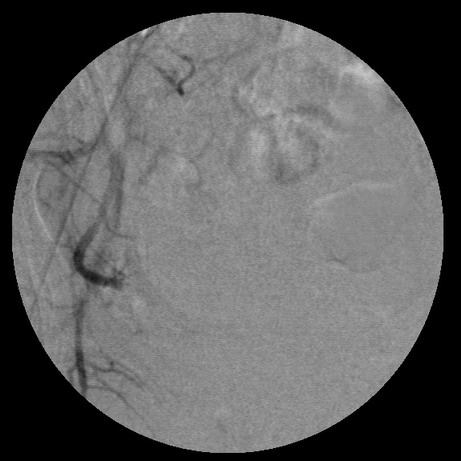

左边没有避开卵巢支啊

栓塞剂用的是进口pva,二瓶,几千块呀,栓塞面积应该不大吧,呵呵